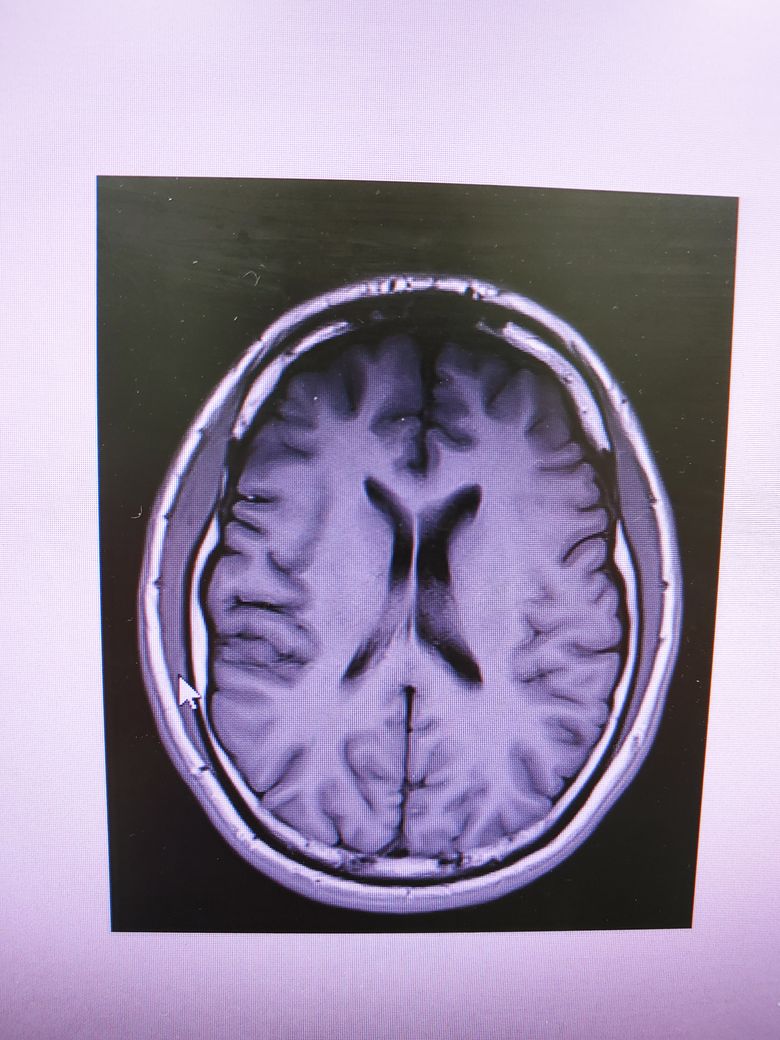

• 4번 째 사진

4컷만으로는 MRI에 대한 충분한 판독이 어렵지만 큰 이상은 없는것으로 보입니다.

특이 이상소견은 보이지 않으나 mri의 경우 4장으로 판단하는 것이 아닌 각 단면마다의 연속적인 영상을 보아야 알수 있습니다. 그리고 각 setting마다 볼수 있는 것도 다르며 보다 명확한 평가를 위해서 담당 선생님께 보다 구체적인 설명을 들으시길 바라며 최근 멍한 증상이 심해졌다면 뇌파 검사 등이 요구될수 있습니다. 우선적으로 기존에 다니셨던 병원을 내원해 진료를 보시고 추가적으로 신경과 내원 또한 고려해볼 수 있습니다. 감사합니다.

올려주신 사진 상에서는 이상소견이 확인되지 않습니다.

MRI의 경우 이렇게 몇컷만 보는것이 아니고 전체를 확인해야하기 때문에 다른 신경과 전문의 진료를 받아보시고 MRI 판독을 요청해보시는게 좋겠습니다.

이미 한번 괜찮다고 들으셨다고 하면 너무 걱정하실 필요는 없습니다. 그리고 MRI사진의 경우 1장만 가지고서 뇌 전체의 이상 여부를 확인할 수는 없답니다. 올리신 사진은 특별한 문제가 없지만 다른 사진에서 이상이 있을 수도 있거든요. 다시 한번 확인을 원하신다면 CD를 가지고 다른 병원에서 추가적인 의견을 들어보셔도 됩니다.